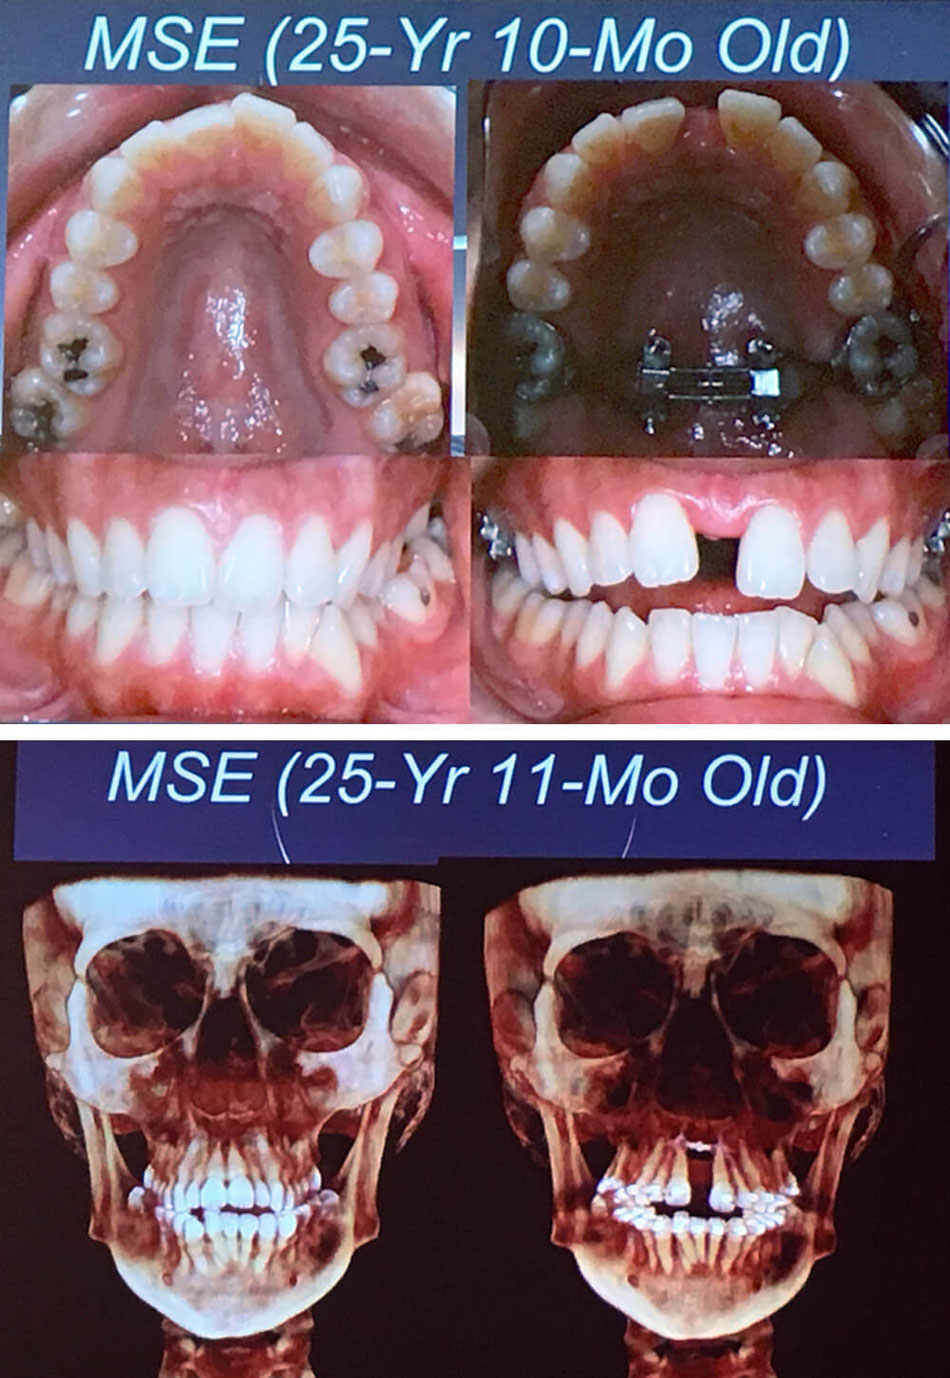

Maxillary Skeletal Expander (MSE) Lemke Orthodontics Sugar Land

day 1 of braces and mse vs day 41 of braces and mse. 33 turns completed Orthodontist Mse He has a modern set of skills, and. For secure fixation and removal of prosthetic screws, implant healing abutments and palatal miniscrews. Maxillary skeletal expansion (mse) is a technique used in orthodontics and dentofacial orthopedics to widen the upper jaw, also known as the. With maxillary skeletal expander (mse), these patients can forgo surgery with the use of 4 tads. Orthodontist Mse.

MSE 86 Days, 84 Turns, Expansion Complete — JAWHACKS Orthodontist Mse Won moon ucla school of. Insight dentalogics (idx) provides services and appliances for advanced orthodontic treatment of their patients, while elevating their professional. He has a modern set of skills, and. He has a very diverse set of experiences that makes him one of the unique orthodontists of south korea. Home > products > acr orthodontic system > mse. Maxillary. Orthodontist Mse.